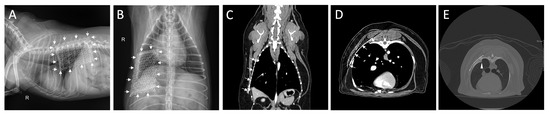

2. Case Description